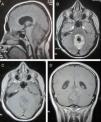

Caso clínicoPaciente de 30 años que tras sufrir traumatismo craneoencefálico leve presentó cefalea, diplopía y ataxia. Los estudios de tomografía computarizada y resonancia magnética cerebral revelaron una tumoración a nivel del cuarto ventrículo con sangrado intralesional y áreas de calcificación. La paciente fue intervenida realizándose extirpación tumoral macroscópicamente completa. El estudio anatomopatológico mostró un tumor glioneuronal formador de rosetas del cuarto ventrículo.

Case reportA 30-year-old patient was admitted after suffering mild traumatic brain injury (TBI) had headache, diplopia and ataxia. Studies of computed tomography and magnetic resonance imaging revealed a tumor at the fourth ventricle with intralesional bleeding and areas of calcification. She was operated performing macroscopically complete tumor resection. Pathologic examination showed a rosette-forming glioneuronal tumor of the fourth ventricle.